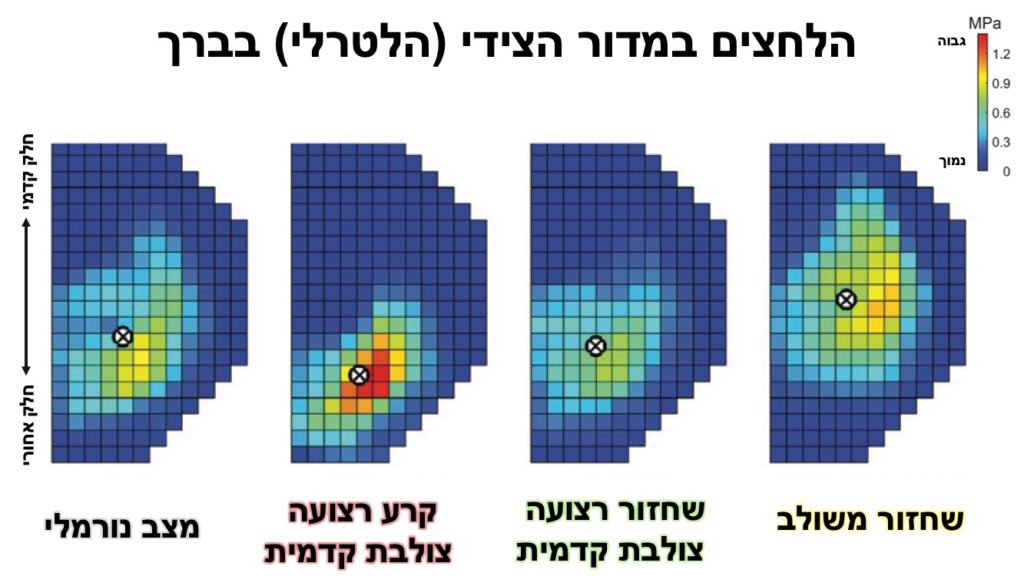

- הניתוח המשולב משנה את אופן פיזור הכוחות במדור הצידי בברך ביחס לברך נורמלית (כוחות גבוהים יותר בחלקים הקדמיים יותר של המדור).

- עם זאת, ברוב שילובי הכוחות שנבדקו, הניתוח המשולב אינו מעלה את הלחץ (contact stress) המקסימלי במדור.

- ניתן לראות באופן ברור את עליית הלחץ במדור הצידי לאחר קרע של הרצועה הצולבת הקדמית, מה שמסביר את השינויים השחיקתיים בברכיים לא יציבות בהעדר רצועה צולבת קדמית.

- בנוסף, ניתן לראות שניתוח מבודד לשחזור רצועה צולבת קדמית מוריד את הלחצים במדור הצידי חזרה ללחצים נורמלים.